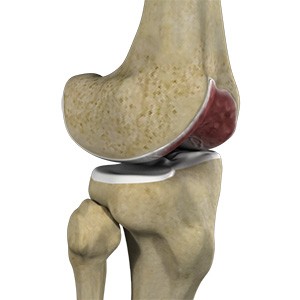

Picture of Chondral (Articular Cartilage Defects)

Chondral (Articular Cartilage Defects)

The articular or hyaline cartilage is the tissue lining the surface of the two bones in the knee joint. Cartilage helps the bones move smoothly against each other and can withstand the weight of your body during activities such as running and jumping. Articular cartilage does not have a direct blood supply to it, so has less capacity to repair itself. Once the cartilage is torn it will not heal easily and can lead to degeneration of the articular surface, leading to the development of osteoarthritis.